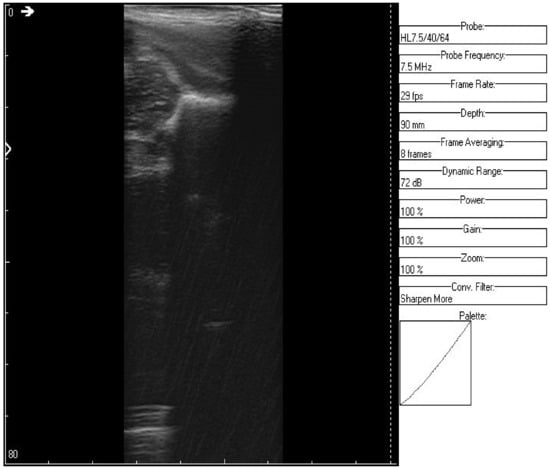

The original recording is displayed in Figure 3. As a first processing step, a color palette has been added to the original ultrasound in order to better highlight the noise and noise-free zones (Figure 4). The wavelet-based filter, as described in Section 2, is applied, and the processed image is shown in Figure 5.

Figure 3. Original recorded data.

Jpm 12 01328 g003

Figure 4. Original data with an added color palette. A region of interest containing some speckle grains was encircled in yellow.

Jpm 12 01328 g004